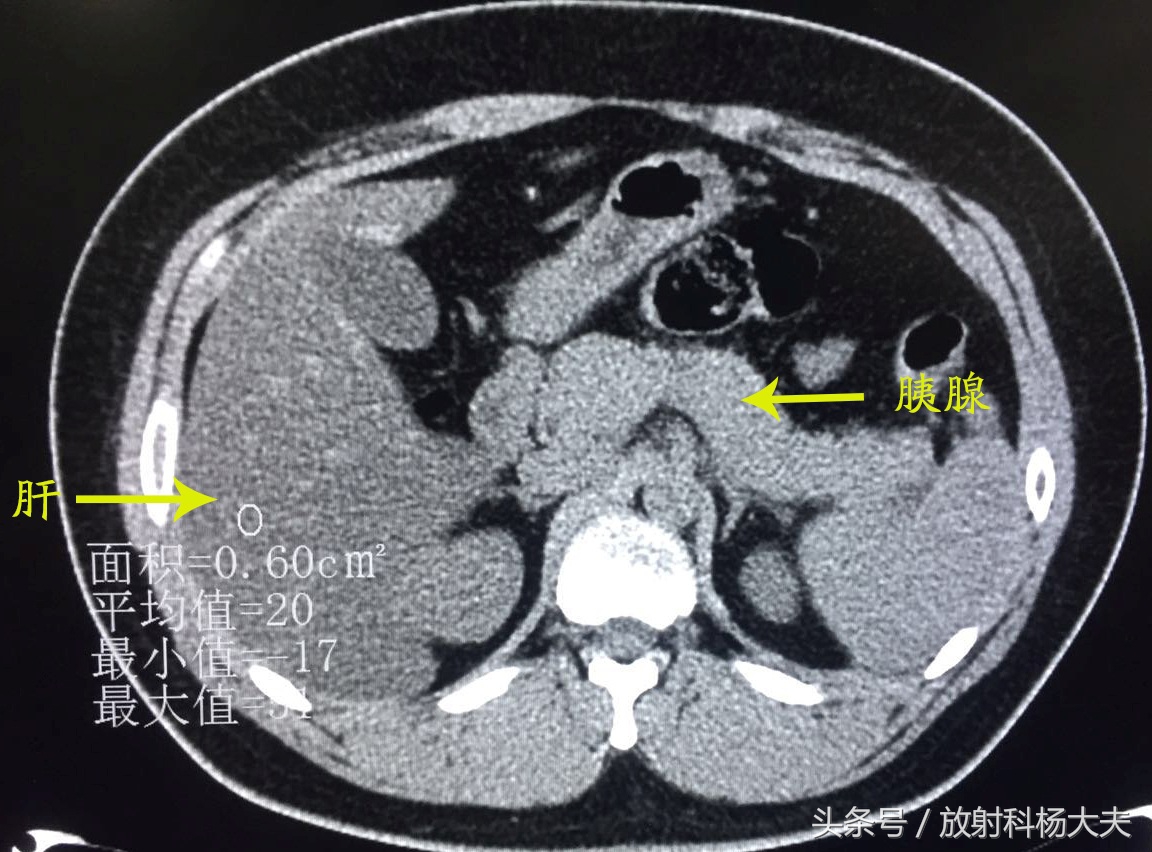

当时治疗后复查:

胰周渗出基本吸收了,脂肪肝较前也有所好转了。